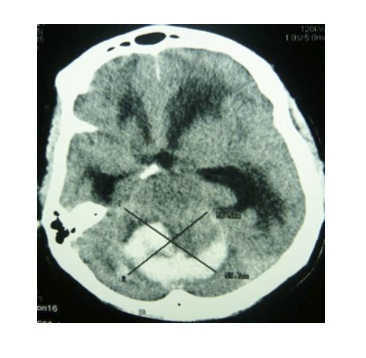

un homme de 56 ans, issu d’un milieu rural, hypertendu est admis le 22 juin 2011 au service de réanimation polyvalente. Avant son admission dans le service il présente un trouble de l’équilibre avec une pression artérielle de 250 /140 mmHg, puis s’installe rapidement un coma. Le patient a bénéficié d’un traitement par nicardipine intraveineux et du mannitol 10 %. Il a été ensuite transporté de façon non médicalisée vers la ville de Pointe noire pour conditionnement en vue de son transfert à Brazzaville. A l’arrivée à Pointe noire, le patient présente un coma profond et la saturation pulsée en oxygène est à 86 % ; il est bien coloré et l’état hémodynamique stable : fréquence cardiaque à 76 bpm et pression artérielle à 150/100 mmHg. Une intubation orotrachéale est réalisée après une induction à séquence rapide utilisant l’étomidate et la célocurine. La sédation associant midazolam et fentanyl est mise en route, ainsi qu’une ventilation mécanique. Le bilan biologique objective des leucocytes à 14700/ mm3, un taux d’hémoglobine de 16,6 g/dl, un taux d’hématocrite à 48,4 %, un nombre de plaquettes évalué à 319 000 ; une natrémie estimée à 136,9 mEq/l, une kaliémie de 5,0 mEq/l ; un taux de prothrombine de 84 %. L’électrocardiogramme montre une tachycardie régulière sinusale. La tomodensitométrie cérébrale révèle un hématome cérébelleux de 59 mm × 39 mm avec effet de masse sur le quatrième ventricule et une dilatation triventriculaire sus-jacente (figure 1). Au regard de ces aspects tomodensitométriques, un transfert vers le service de réanimation polyvalente du Centre Hospitalier Universitaire de Brazzaville est demandé pour une prise en charge optimale. A l’arrivée au service de réanimation polyvalente, la sédation était de niveau 6 selon le score de Ramsay [5], la température à 37° C, la SpO2 à 98 %, la fréquence cardiaque à 100/min et la tension artérielle de 160/90 mm Hg. La tomodensitométrie de contrôle mettait en évidence un hématome du cervelet avec une hydrocéphalie importante (figure 2). Aprèsavis du neurochirurgien, une dérivation externe du liquide céphalo-rachidien (LCR) a été réalisée, produisant quotidiennement en moyenne 400 ml de LCR. Une amélioration de l’état neurologique a été notée au deuxième jour, le score de Glasgow était évalué à 8/10, le patient étant toujours intubé. Le patient était décédé à j12 d’hospitalisation, des suites d’une pneumopathie hypoxémiante nosocomiale tardive, diagnostiquée à j8.